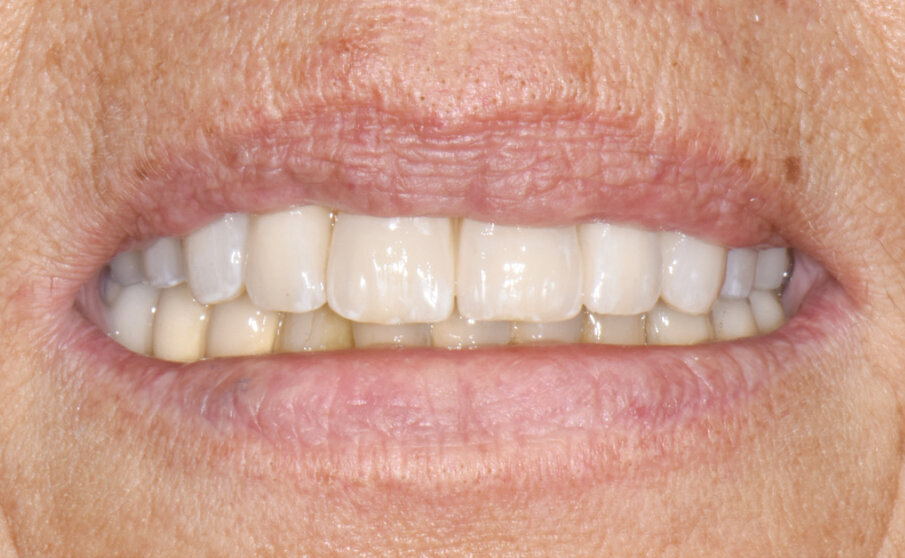

Dopo aver tolto le suture (Fig. 13) e consegnato il Toronto definitivo (Figg. 14, 15), si effettuano due visite di controllo a 2 e 4 mesi di distanza in cui si valutano il rapporto occlusale, il serraggio delle viti di connessione effettuato con chiave dinamometrica tarata a 20 Ncm, RX di controllo e la chiusura degli alloggi delle viti con resina composita (al controllo dopo 4 mesi).

Fig. 14 - Protesi definitiva tipo Toronto in sede (a 7 giorni dall’intervento chirurgico).

Fig. 15 - Protesi definitiva tipo Toronto in sede (a 7 giorni dall’intervento chirurgico).